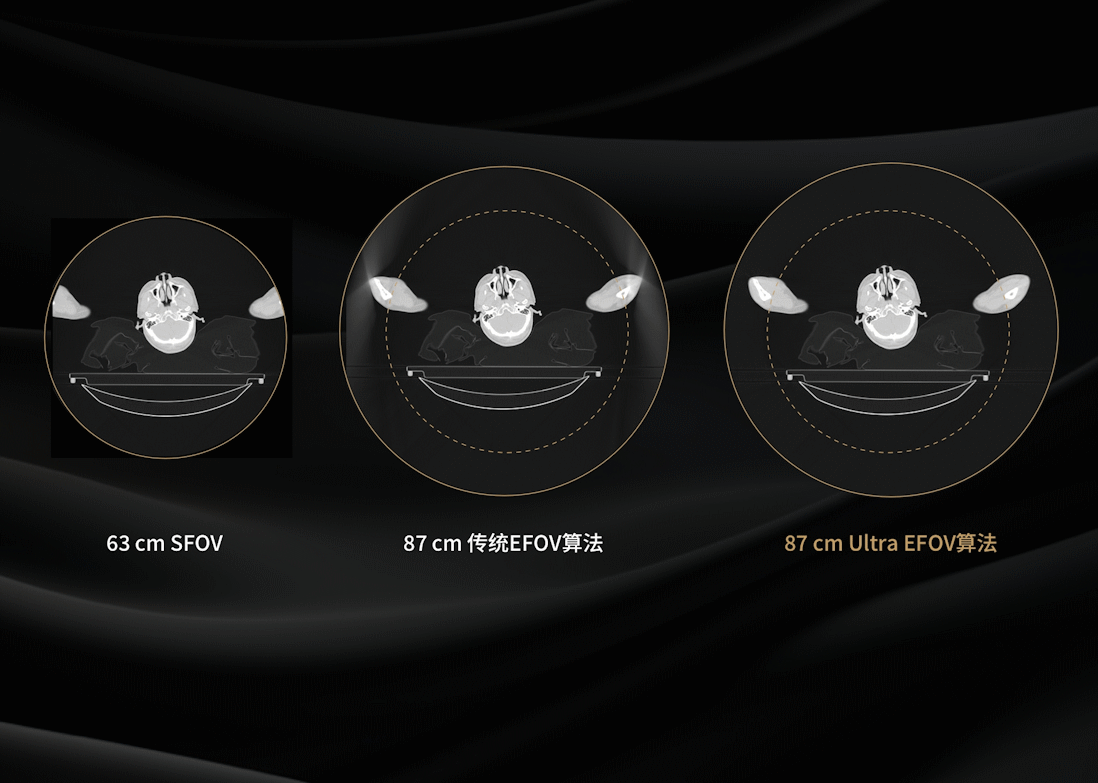

相较于常规CT系统,扫描视野提升26%*,对大体重、偏中心摆位等特殊患者模拟定位扫描呈现更加完整的解剖结构

基于深度学习神经网络充分优化扩展视野部分“环形带”投影,有效消除截断伪影,大幅提升全视野成像质量和定量准确性